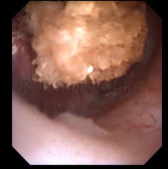

The Images Below are of Kidney Stones taken as snapshots from the video recording of RIRS Surgery done at our hospital with Digital Flexible Ureteroscopes, Flex XC and Flex XC S.